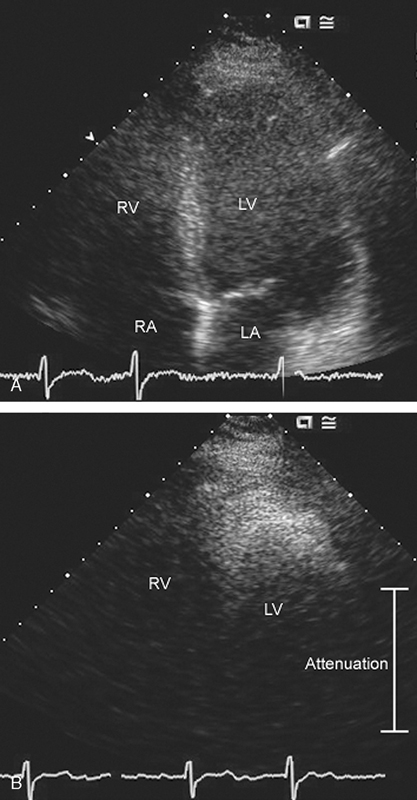

فحوصات تشخيصية لبعض امراض القلب والشرايين التاجية